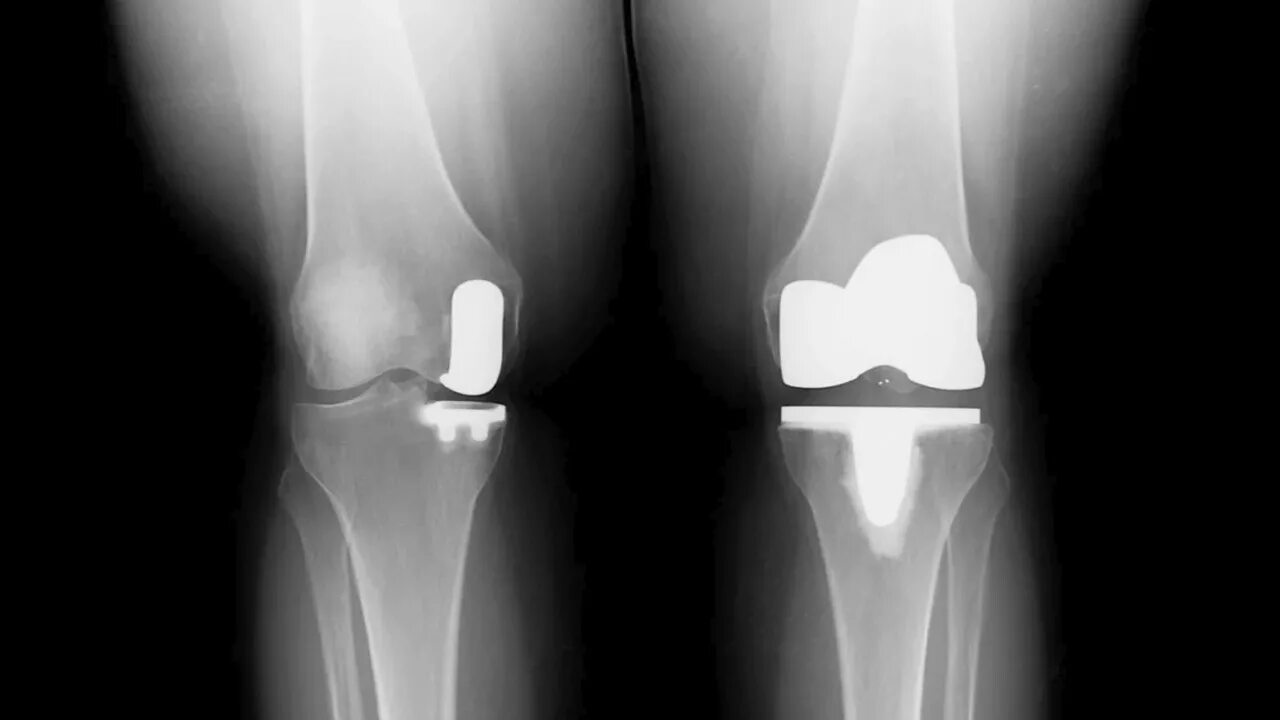

Эндопротезирование мкб 10 у взрослых